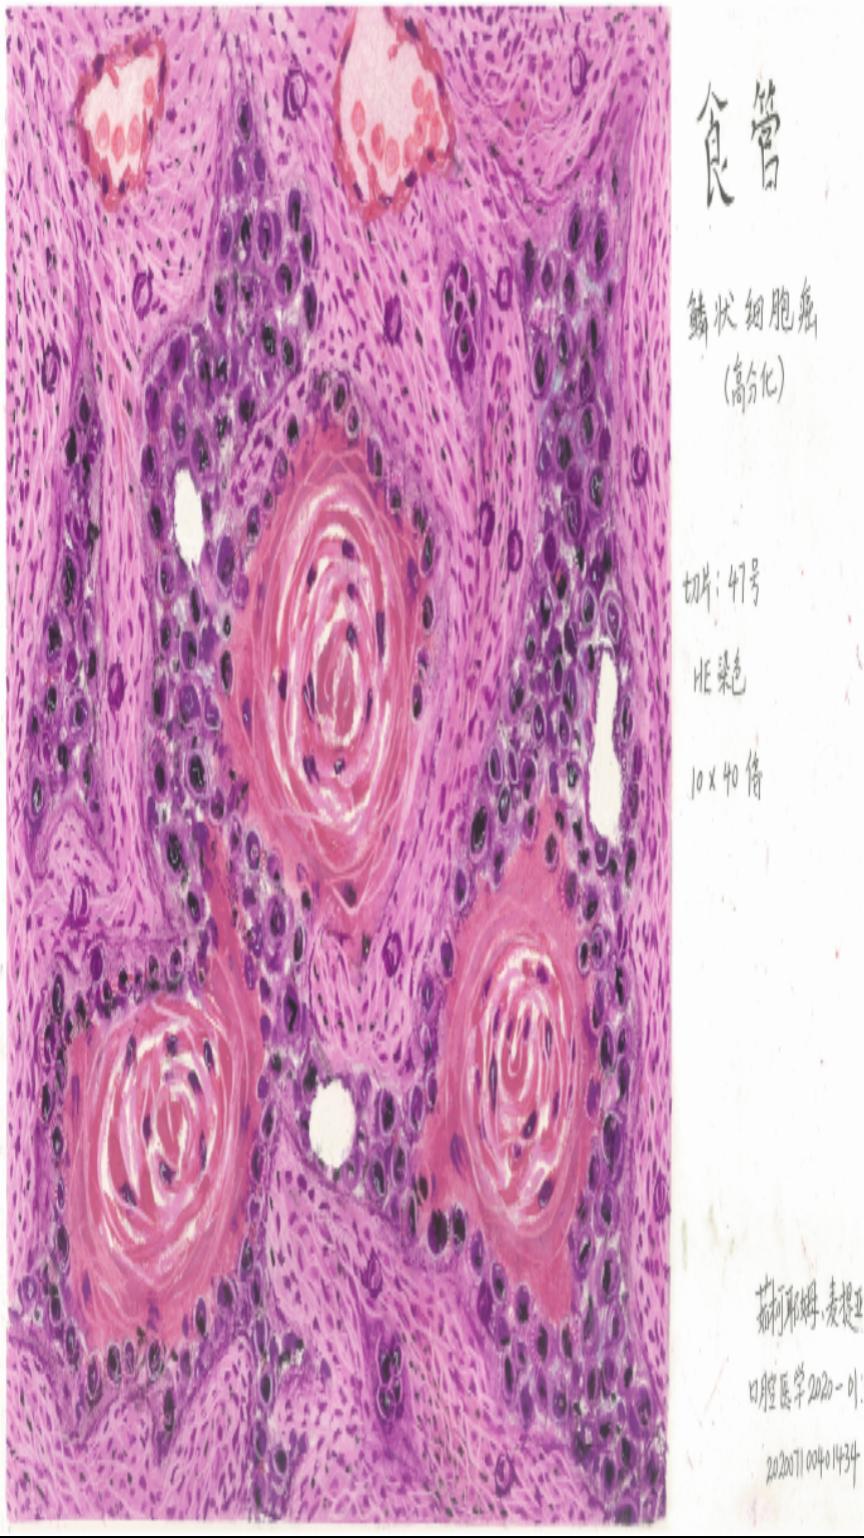

《食管鳞状细胞癌》